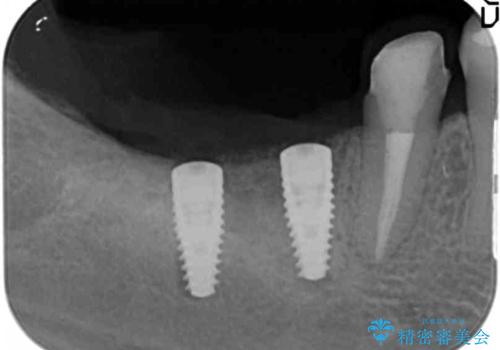

- 失ってしまった奥歯の咬合機能の回復を求めて来院されました。

骨の幅が十分にないのでインプラント治療に伴い、人工骨の造成を同時に計画します。

インプラントは高い確率で骨に結合し、しっかりとした咬合力を回復することができます。

長年安心してしっかりと噛んでいただけるよう今回は骨を増成する治療計画としました。